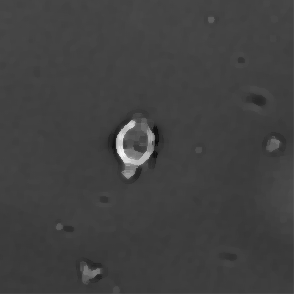

Figure 3: Original images of sequence is example of high dynamics of cell behavior affecting on contrast properties

The Fig.3 is representing couple of frames of sample image sequence with relatively high contrast between foreground and can be segmented with almost 95% accuracy with any method we used. Frame 1 of sample sequence presented at Fig.3(a) contain regions of hyper contrast pixels. In this case such condition does not affect on valid recognition since they are belong to object and present on margins of it and differs well from background. For Frame 2 there is absence of such pixels (Fig.3(b)) and this conditions also makes segmentation possible in relatively inflexible filtering conditions. The Frame 2 has relatively low contrast however it is seen that after filtration applied on image we achieve good difference of core and cell body compared to background as it presented at Fig.4 .